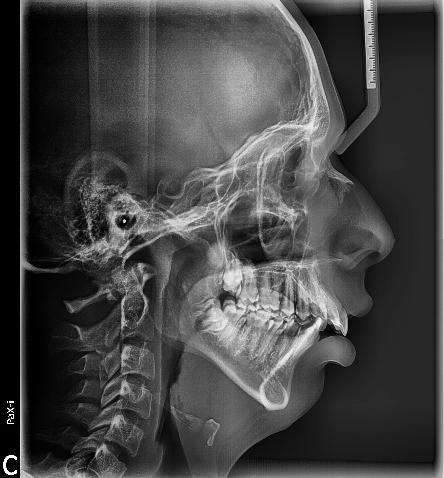

Figura 1. Perfil de inicio. Figura 2. Cefálica lateral.

Se presenta un paciente en edad de 15 años y 2 meses. Refiere que acude a consulta por evaluación. En la valoración extraoral presente la hiperdivergencia y sus posiciones dentales (Figura 1), tiene un perfil convexo con hiperactividad del músculo mentoniano e incompetencia labial, y en la radiografía lateral de cráneo inicial (Figura 2) se aprecia el patrón esquelético clase II severo.